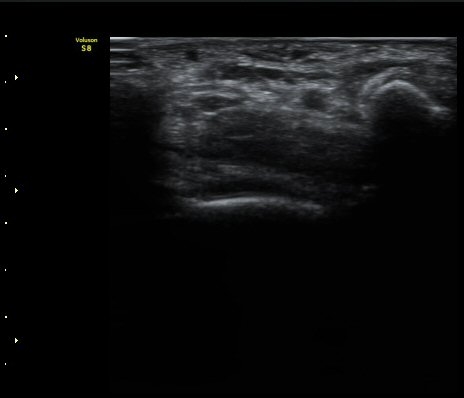

ÃÊÀ½ÆÄ °Ë»ç